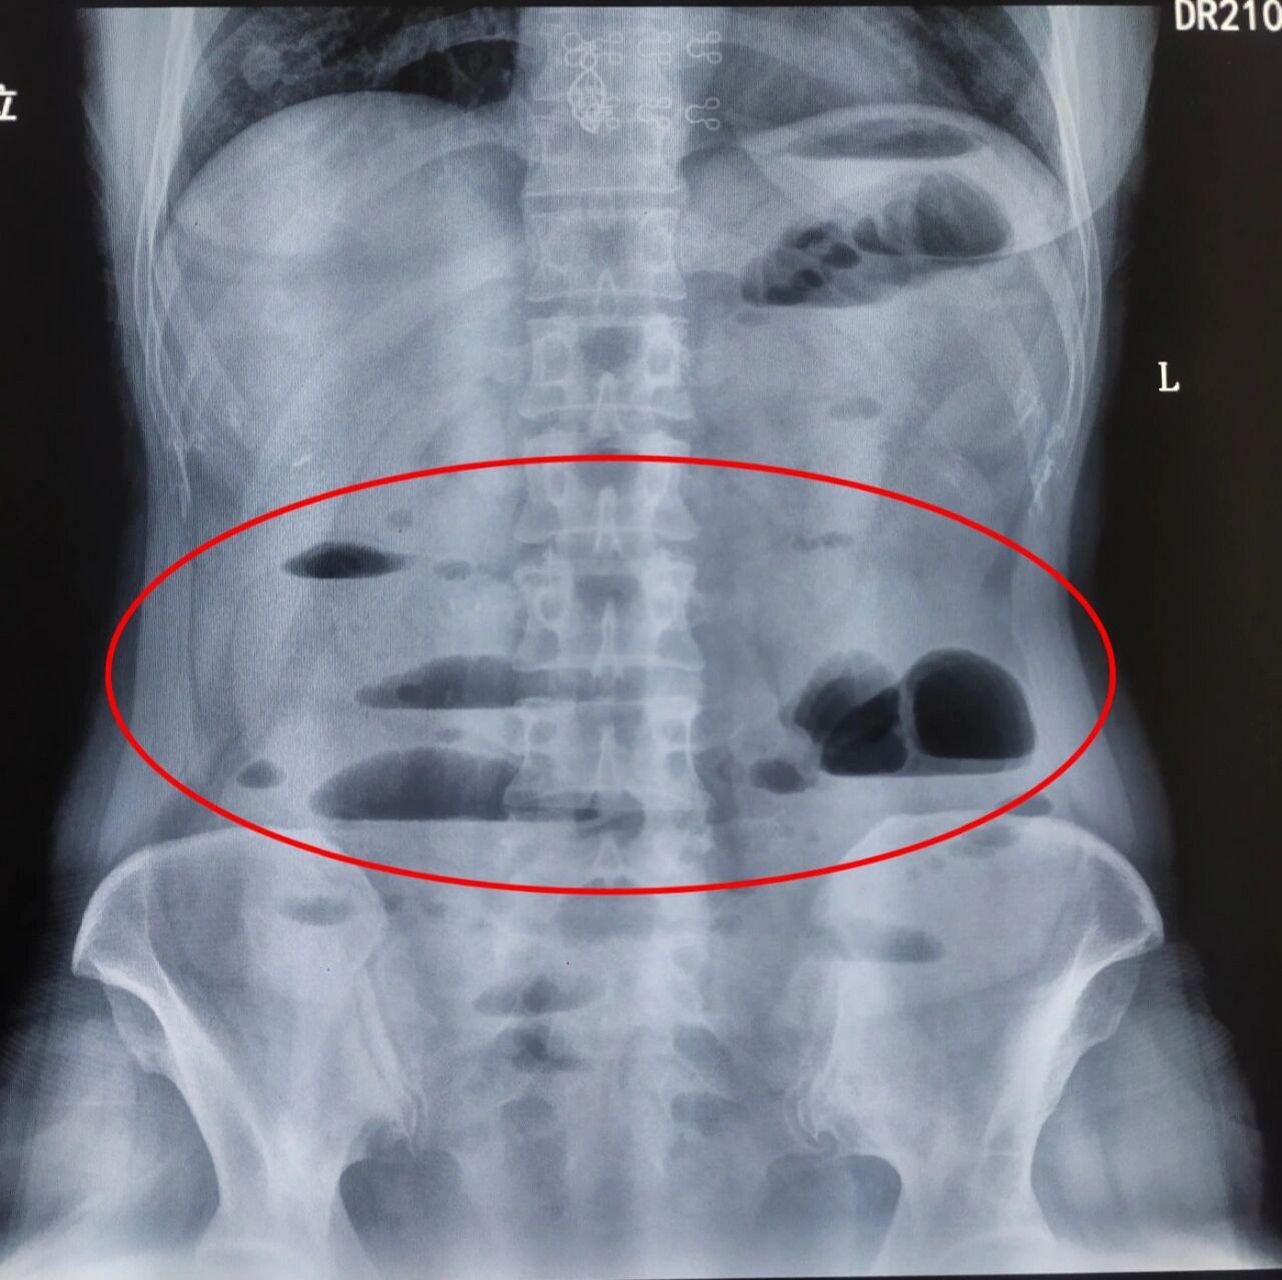

小肠梗阻(立位)

我在急诊值班:肠梗阻立位平片